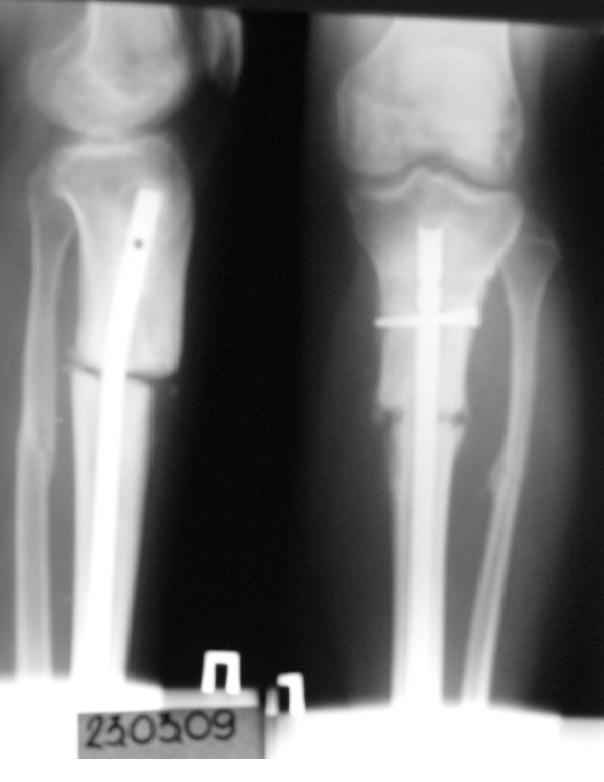

История следующая: женщина (медработник)сбита машиной 7.06.08 - о.перелом обоих костей голени в/3 со смещением. В ПДО ПХО раны,вытяжение за пяточную кость. После заживления раны 20.06.08 выполнен остеосинтез блокирующем стержнем. в течение первого месяца после травмы сохранялась субфебрильная температура на фоне приема антибиотиков. Затем температура стабилизировалась.Б-ая как положено ходила в гипсе на костылях. На контрольных рентгенограммах консолидация не достигалась, иммобилизация продлевалась. Пациентка на себе опробовала все препараты костной регенерации. В марте удален один из фиксирующих винтов. На сегодняшний день идет 11 мес. после травмы. Решается вопрос о инвалидности. Буду благодарен за предложения по дальнейшему ведению больной. Операция?

Сегодня мы имеем консолидированный перелом малоберцовой кости, являющийся распоркой и отстутствие консолидации большеберцовой кости, и ваша динамизация гвоздя, выполненная с опозданием не ришила проблем.

Не нужно ждать так долго, давно пора делать реостеосинтез.

Не показан нижний конец гвоздя. Винты надо было убирать из него, зачем из верхнего-то отломка.

Сейчас надо перештифтовать. При удалении взять посев. Не просто рассверлить старый канал и поменять гвоздь на больший, а устранить все смещения при помощи отклоняющих винтов. Рассверлить надо. Малоберцовую, наверно, лучше пересечь внизу.

Учитывая общие сроки с момента травмы ситуацию надо расценивать как несросшиийся перелом, тогда вся тактика будет понятно (реостеосинтез с рассверливанием к/канала). С уважением Ерсин Жунусов.